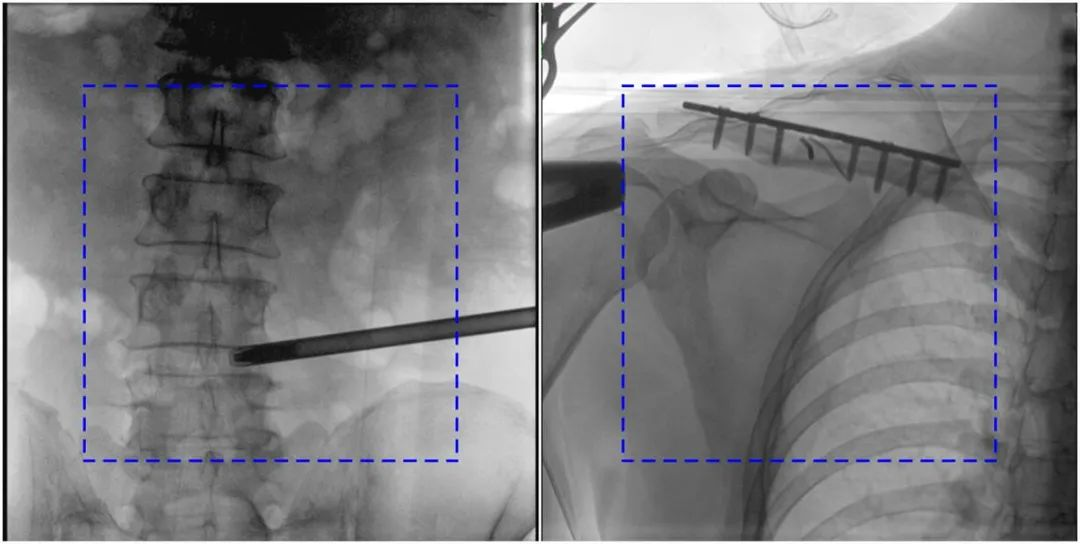

與傳統的21CM×21CM成像尺寸相比,普愛(ài)醫療大平板一體式C形臂具有30CM×30CM更大成像尺寸,能夠一次成像5.5節椎體,呈現更全面的影像信息,即便是手術(shù)經(jīng)驗不豐富的年輕醫生也能通過(guò)圖像迅速判斷椎體節段、定位手術(shù)部位,避免因為視野不足而造成的多次定位、反復曝光,提高效率的同時(shí)避免過(guò)量攝入輻射。

普愛(ài)醫療大平板一體式C形臂圖像與傳統圖像對比(藍色虛線(xiàn)內為傳統21CM×21CM平板的成像區域)